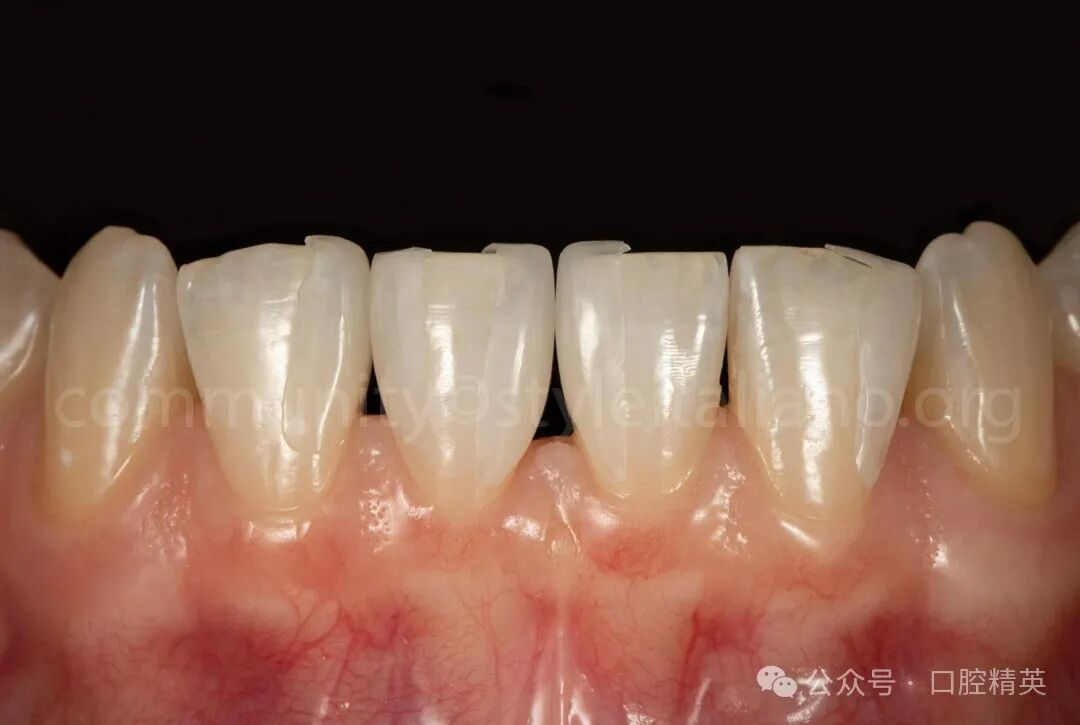

图7 粘接完成后,调颌、抛光。

图8 抛光也是在橡皮障隔离下进行的,这有助于最大限度地降低牙龈损伤的风险,并提供了更有效和可控的工作流程。